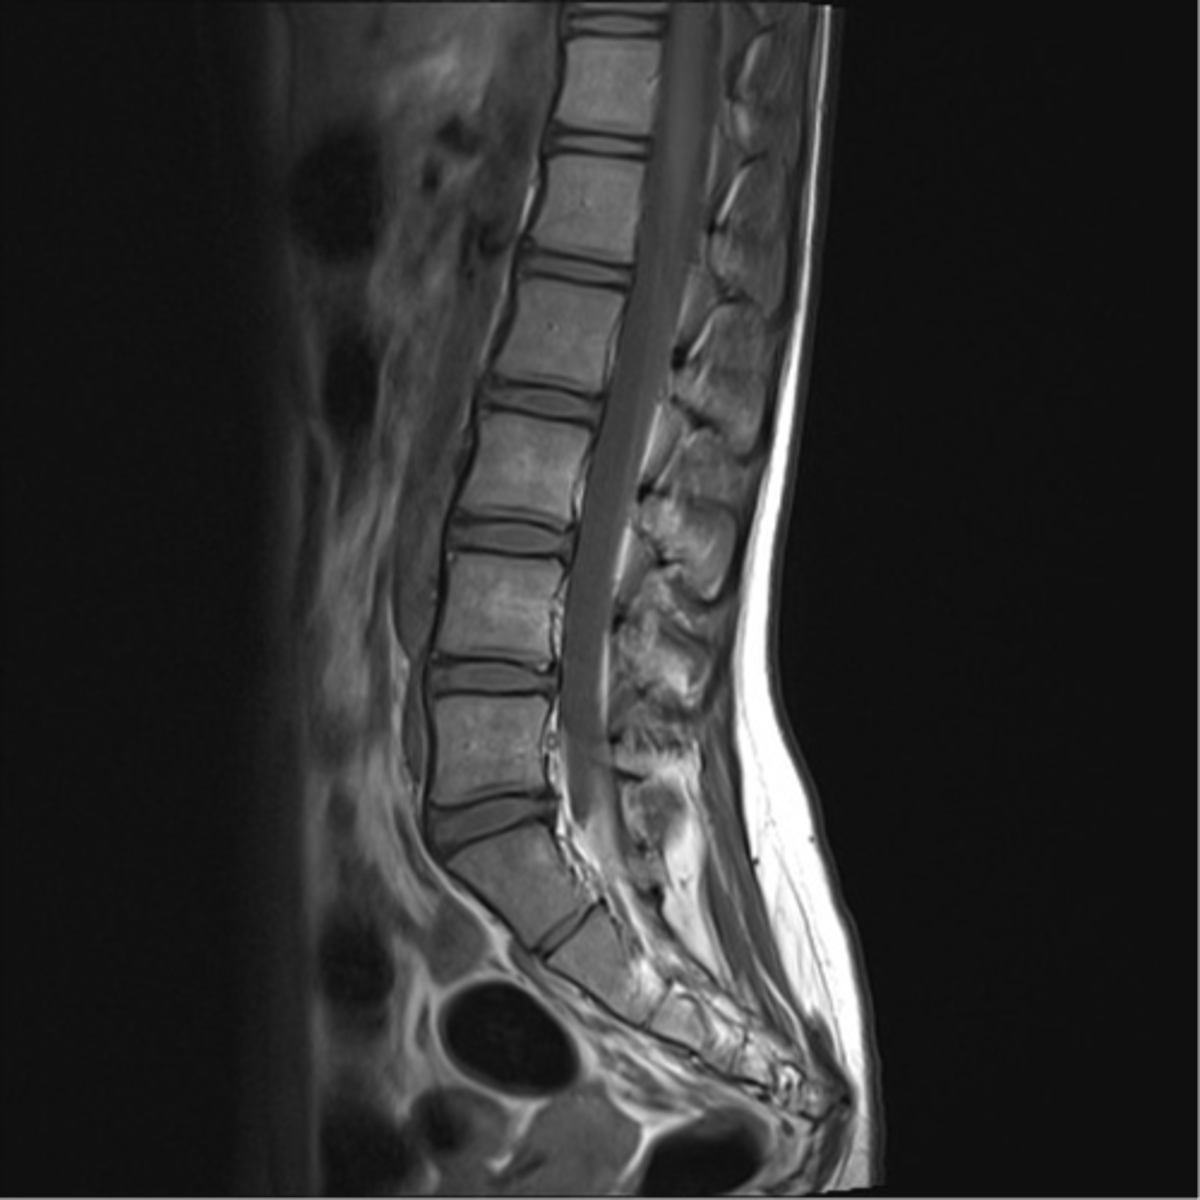

describe

normal MRI